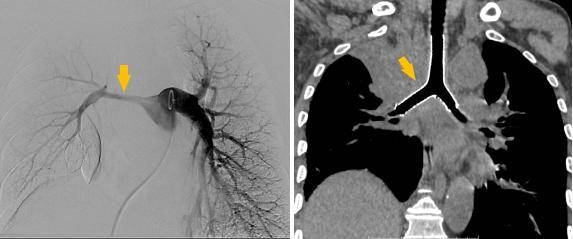

术前受压变窄的右肺动脉和中央气道

潍坊市第二人民医院完成首例气管支架、肺动脉覆膜支架同期植入术